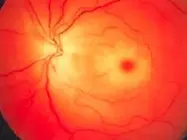

Wet macular age related degeneration

Male nondiabetic patient aged 75 years old presented by this picture in the left eye

What is treatment in this condition? Intravitreal injection of AVGF

Fundus:

- Dry: drusen, RPE change

- Wet: gray-yellow CNV under retina of posterior pole, associated with dark red subretinal hemorrhage, which covers CNV sometimes

FFA: CNV leakage, bleeding